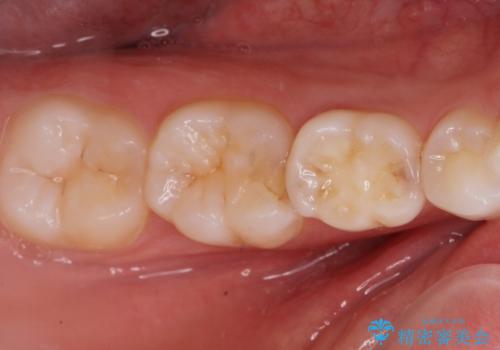

歯が染みる。セラミックインレー治療。

- 歯が染みるとの事で来院。

レントゲンを撮影したところ虫歯がありましたので拡大鏡下で虫歯を取り除いた後、e-maxインレーにて治療を行いました。

手前の歯は乳歯でしたが、患者様と相談しなるべく長持ちさせたいとの事でしたのでe-maxインレーでの治療となりました。

適合の良い詰め物が入りました。